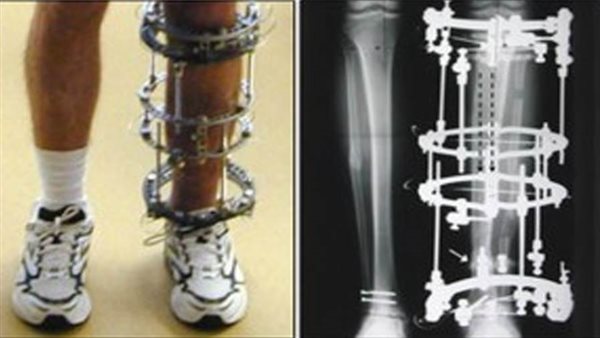

ينظم المعهد العربي للتنمية المهنية المستدامة (معتمد) التابع لاتحاد الأطباء العرب، الْيَوْمَ الجمعة الموافق 16 أكتوبر، ملتقى علمي لتنمية مهارات المتدربين في اصلاح تشوهات واطالة العظام عبر تقنية "زووم" على الإنترنت؛ وذلك بمشاركة خبراء من الولايات المتحدة، والمكسيك، وباكستان، وعدد من مختلف دول العالم.

ويستهدف الملتقى العلمي تنمية مهارات أطباء العظام في مصر والوطن العربى ، ورفع كفاءاتهم من خلال تبادل الخبرات، وإطلاعهم على المستجدات الطبية في هذا المجال.

في سياق متصل، قال معهد معتمد إن باب الحجز لا يزال مفتوحا للتسجيل في الدفعة الحادية عشر من الدبلوم المهنى فى اصلاح تشوهات واطالة العظام، والذي يجرى التدريس خلاله بطريقة نظام التعليم الهجين، حيث يتم استخدام احدث تقنيات التعليم التفاعلى عن بعد، إضافة الى التدريب على المهارات الاكلينيكية والجراحية فى ورش عمل ينظمها المعهد حسب الاجراءات الاحترازية المتبعة طبقا لتعليمات الجهات المختصة. وقال للدكتور أسامة رسلان أمين عام اتحاد الأطباء إن المحاضرات العلمية لمعهد معتمد تستهدف تنمية مهارات الأطباء، واطلاعهم على كافة المستجدات الطبية في مجال جراحة العظام .